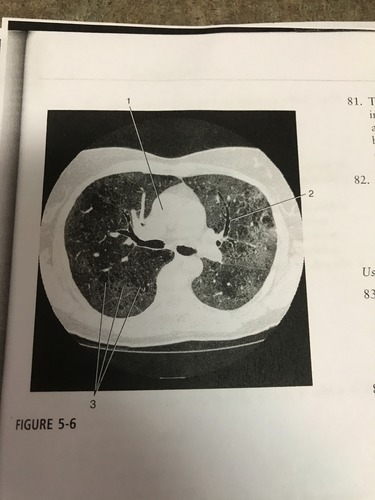

The pathological process indicated by number 3 on the figure most likely corresponds to:

A) atelectasis

B) lymphadenopathy

C) pleural effusion

D) ground- glass opacity

Number 1 on the figure corresponds to what?

A) right atrium

B) pulmonary trunk

C) ascending aorta

D) right ventricle

This HRCT image of the chest was most likely acquired with a section width of:

A) 1mm

B) 5mm

C) 7mm

D) 10mm

Number 2 on the figure corresponds to which of the following?

A) Left mainstem bronchus

B) anterior segment of the left upper lobe bronchus

C) posterior segment of left upper lob bronchus

D) anterior segment of left lower lobe bronchus